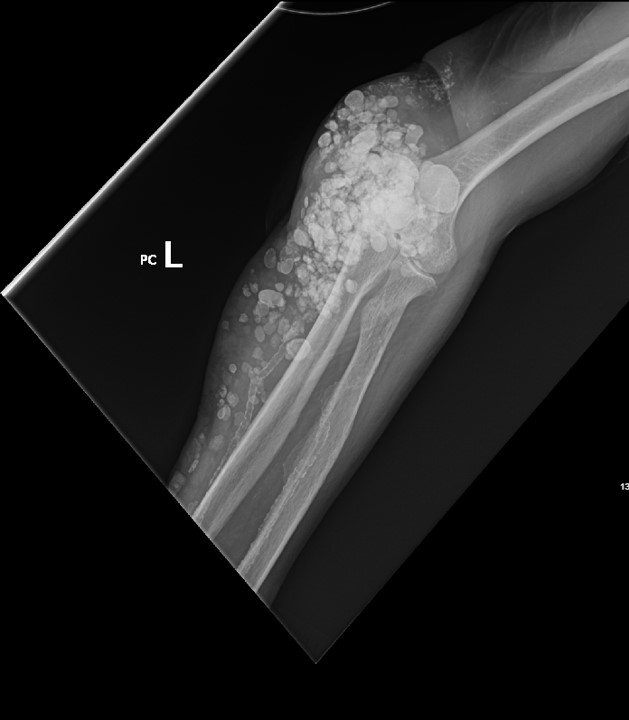

Calcinosis cutis is a condition in which calcium-phosphate salt deposits are formed in cutaneous and subcutaneous tissue. A subtype, metastatic calcinosis cutis, can occur in patients with disorders that cause hypercalcemia or hyperphosphatemia such as end stage renal disease. We present a case of a 67-year-old man with end-stage renal disease (ESRD) on dialysis who presented to the emergency department with a draining left elbow wound. On exam, he had irregular, firm nodules palpable in the subcutaneous tissue of both large and small joints. The presence of calcinosis cutis on imaging and lack of other findings suggesting infection led to outpatient wound care treatment. Recognizing the appearance of calcinosis cutis on imaging and conditions that present with calcinosis cutis is important for the emergency physician.

Topics: Calcinosis cutis, end-stage renal disease, ESRD, dialysis, subcutaneous calcifications.